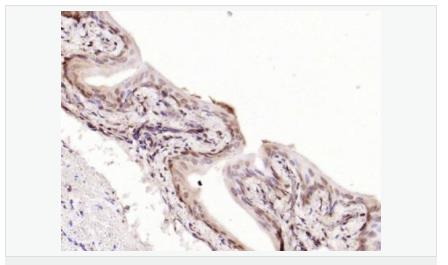

| 產(chǎn)品應(yīng)用 | WB=1:500-2000 ELISA=1:5000-10000 IHC-P=1:100-500 IHC-F=1:100-500 Flow-Cyt=1μg /test IF=1:100-500 (石蠟切片需做抗原修復(fù)) not yet tested in other applications. optimal dilutions/concentrations should be determined by the end user. |